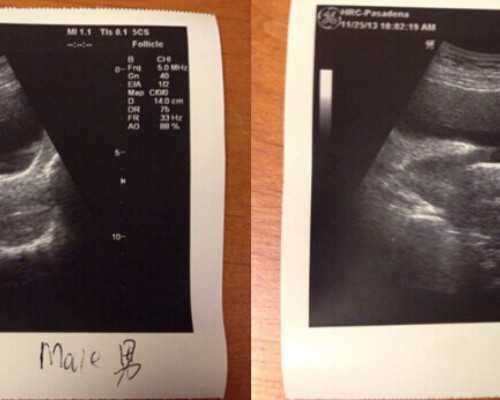

大宝是个女儿,所以二宝想要个儿子,再加上婆婆也想要孙子,反正各种原因吧!我和老公今年开始就准备背二胎了,而且一定要是个儿子!怀孕8周的时候去香港抽血验了性别,在香港林医生验的,现在结果出来了,有检测到相当数量的Y染色体,是个儿子!备孕成功,分享下检验吧(这个是我备孕的一个心得,不能说百分百成功哈,只能说参考参考吧)

有的宝妈拿到香港验血结果之后都不知道怎么看香港验血报告单图片,这一张纸能代表什么?其实香港验血就是只是检测Y染色体上的基因,叫做SRY基因。它是Y染色体上的决定男女的DNA片段,只要发现存在SRY基因,就说明了Y染色体的存在,也就正明了男孩。

达雅高化验所检测15项Y染色体DNA物质,其中D代表阳性,ND代表阴性,以以下报告单为例,有检测到Y染色体,所以结果为男孩。报告会有个人信息是可以查询到是不是在化验所检测的。

达雅高作为最早的香港验血化验所,准确率高达99.4%,已经检测有50万个样本,深受宝妈们的信赖。

时代化验所检测16项Y染色体DNA物质,其中+ve代表阳性,-ve代表阴性,以以下报告单为例,验出Y染色体,结果为男孩。没有验出Y就是女